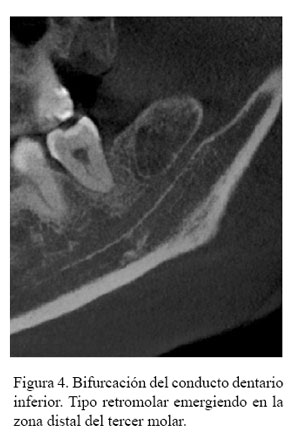

Tipo 1 (Canal retromolar): Consiste en una bifurcación del canal mandibular en la región de la rama mandibular, no alcanza piezas dentales, el conducto realiza una curva y alcanza la región retromolar (Figura 1 (A)).

En la tabla 3 se describe la distribución de la frecuencia del tipo de BCDI donde se encontraron 103 casos del tipo canal retromolar (Figura 2, figura 3 y figura 4); no se encontró ningún caso con el tipo de bifurcación canal bucal-lingual.